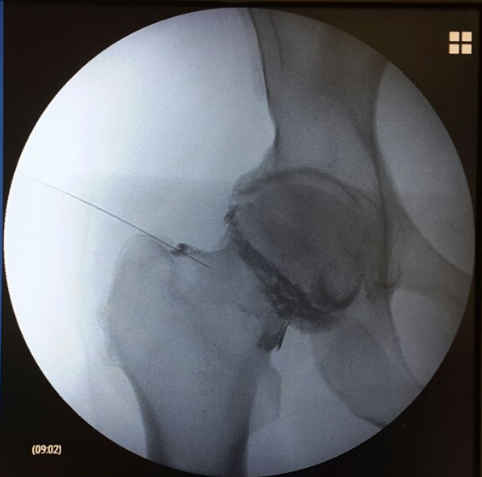

Ασθενής με άλγος αριστερού ισχίου

Ασθενής 58 ετών με άλγος αριστερού ισχίου από έτους συνεχώς επειδυνούμενο. Η ακτινογραφία έδειξε ότι υπάρχει οστεοαρθρίτιδα τελικού σταδίου και προτάθηκε ολική αρθροπλαστική ισχίου. Λόγω υποχρεώσεων της  απεφασίσθη να υποβληθεί σε μια πιο συντηρητική θεραπεία στην παρούσα φάση. Πραγματοποιήθηκε έγχυση ισχίου με υαλουρονικό και παυσίπονα. Η ασθενής ένιωσε άμεσα ανακούφιση που διατηρήθηκε για 6 μήνες και ακολούθως υπεβλήθη σε ολική αρθροπλαστική ισχίου.